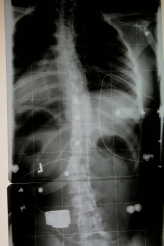

- 15 ° im Korsett (Primärkorrektur nach 14 Tagen)

- Rö.im Korsett.jpg (28.83 KiB) 13962 mal betrachtet

- 50° Cobb.o.K.jpg (29.14 KiB) 13962 mal betrachtet